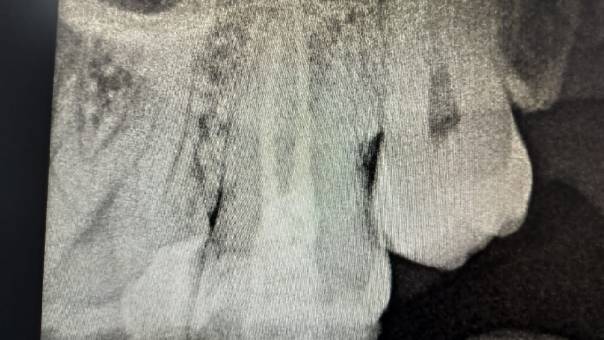

After discussing the findings with the patient, we

recommended a Re-RCT, focusing on the missed distal

canal. This would allow us to eliminate the

infection and restore the tooth’s health.

Clinical Outcome:

The procedure was done comfortably and successfully

on the patient, and recovery was smooth. At

follow-up visits, he reported complete relief from

pain, and healing was progressing as expected.

After Obturation